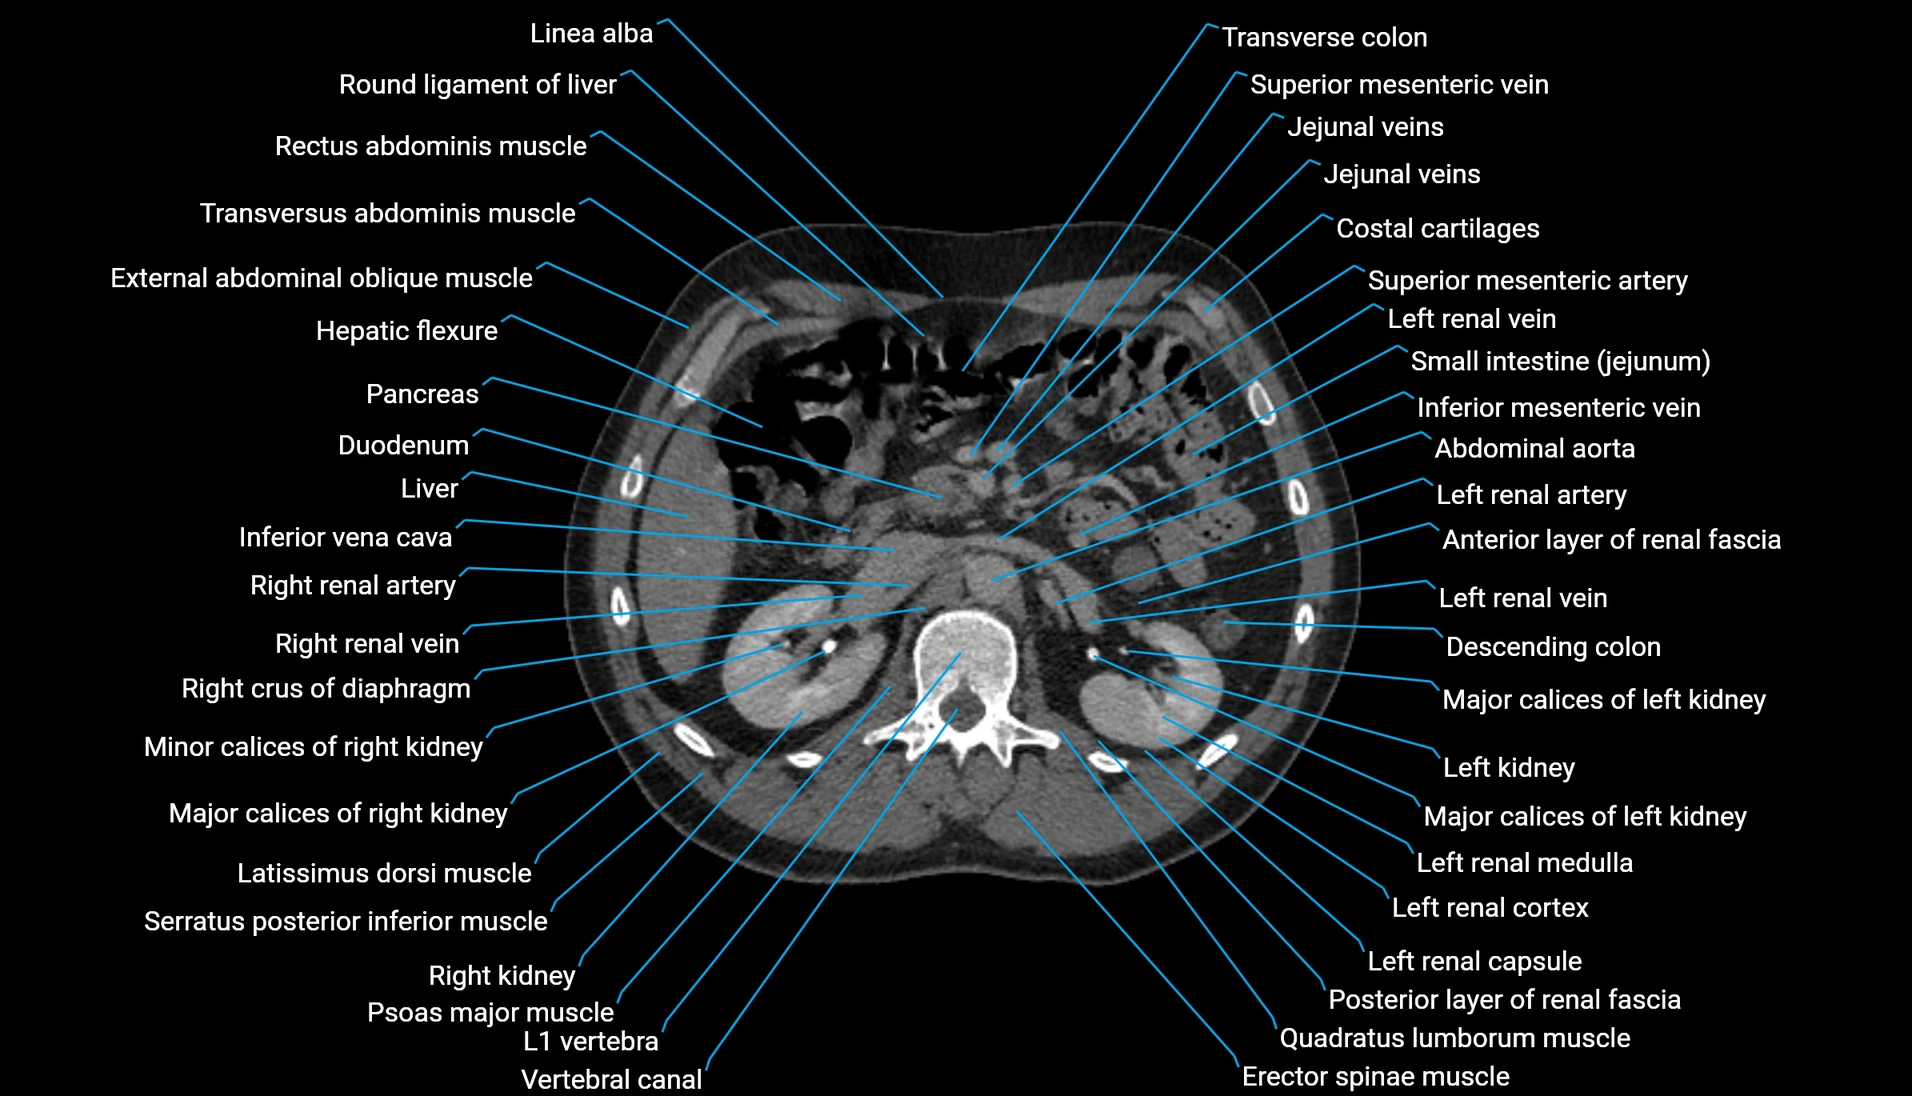

CT Appearance

Non-contrast CT:

-

Demonstrates cortical bone of acetabular rim in excellent detail

Detects fractures, dysplasia, retroversion, or bony overcoverage (pincer impingement)

3D reconstructions used in preoperative hip surgery planning

CT VRT 3D image

CT image